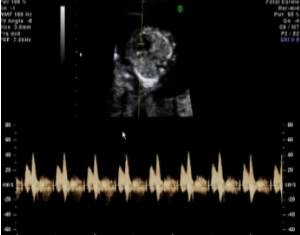

FLUJO TRICUSPIDEO.

Valoración del flujo tricuspideo:

Feto en reposo.

El tórax fetal debe ocupar toda la pantalla

Obtener una imagen de cuatro cámaras apical

No usar Doppler color porque no es preciso en el diagnóstico de regurgitación tricuspídea en el primer trimestre

La ventana del Doppler pulsado debe ser grande (2,0-3,0 mm) y estar posicionada a través de la válvula tricúspide

El ángulo de insonación de la dirección del flujo con respecto al tabique interventricular debe ser menor de 30 grados

La velocidad de barrido debe ser alta (2-3 cm/s), para obtener una forma más ancha

No usar Doppler color porque no es preciso en el diagnóstico de regurgitación tricuspídea en el primer trimestre

La ventana del Doppler pulsado debe ser grande (2,0-3,0 mm) y estar posicionada a través de la válvula tricúspide

El ángulo de insonación de la dirección del flujo con respecto al tabique interventricular debe ser menor de 30 grados

La velocidad de barrido debe ser alta (2-3 cm/s), para obtener una forma más ancha

Patrón normal cuando no hay regurgitación en sístole

Regurgitación durante la mitad de la sístole al menos y con una velocidad de más de 60 cm/s

No confundir con regurgitación tricuspídea:

El flujo producido por las arterias aorta o pulmonar, que en este momento gestacional llega a una velocidad máxima de 50 cm/s

La “espícula” reversa generada con el cierre de la válvula

Regurgitación tricuspídea

En las semanas 11-13 se encuentra aproximadamente en:

- Fetos euploides 1%

- Fetos con trisomía 21 - 55%

- Fetos con trisomía 18 - 30%

- Fetos con trisomía 13 - 30%

- La gestación es de 11 en lugar de 13 semanas

- La translucencia nucal fetal está aumentada